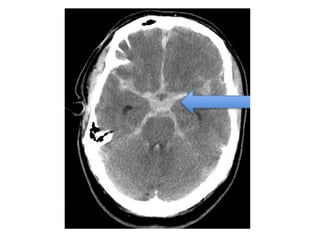

NECT shows hyperdense internal veins and bilateral (R > L) thalami

hypodensities , compatible with dural vein thrombosis and venous

infarction